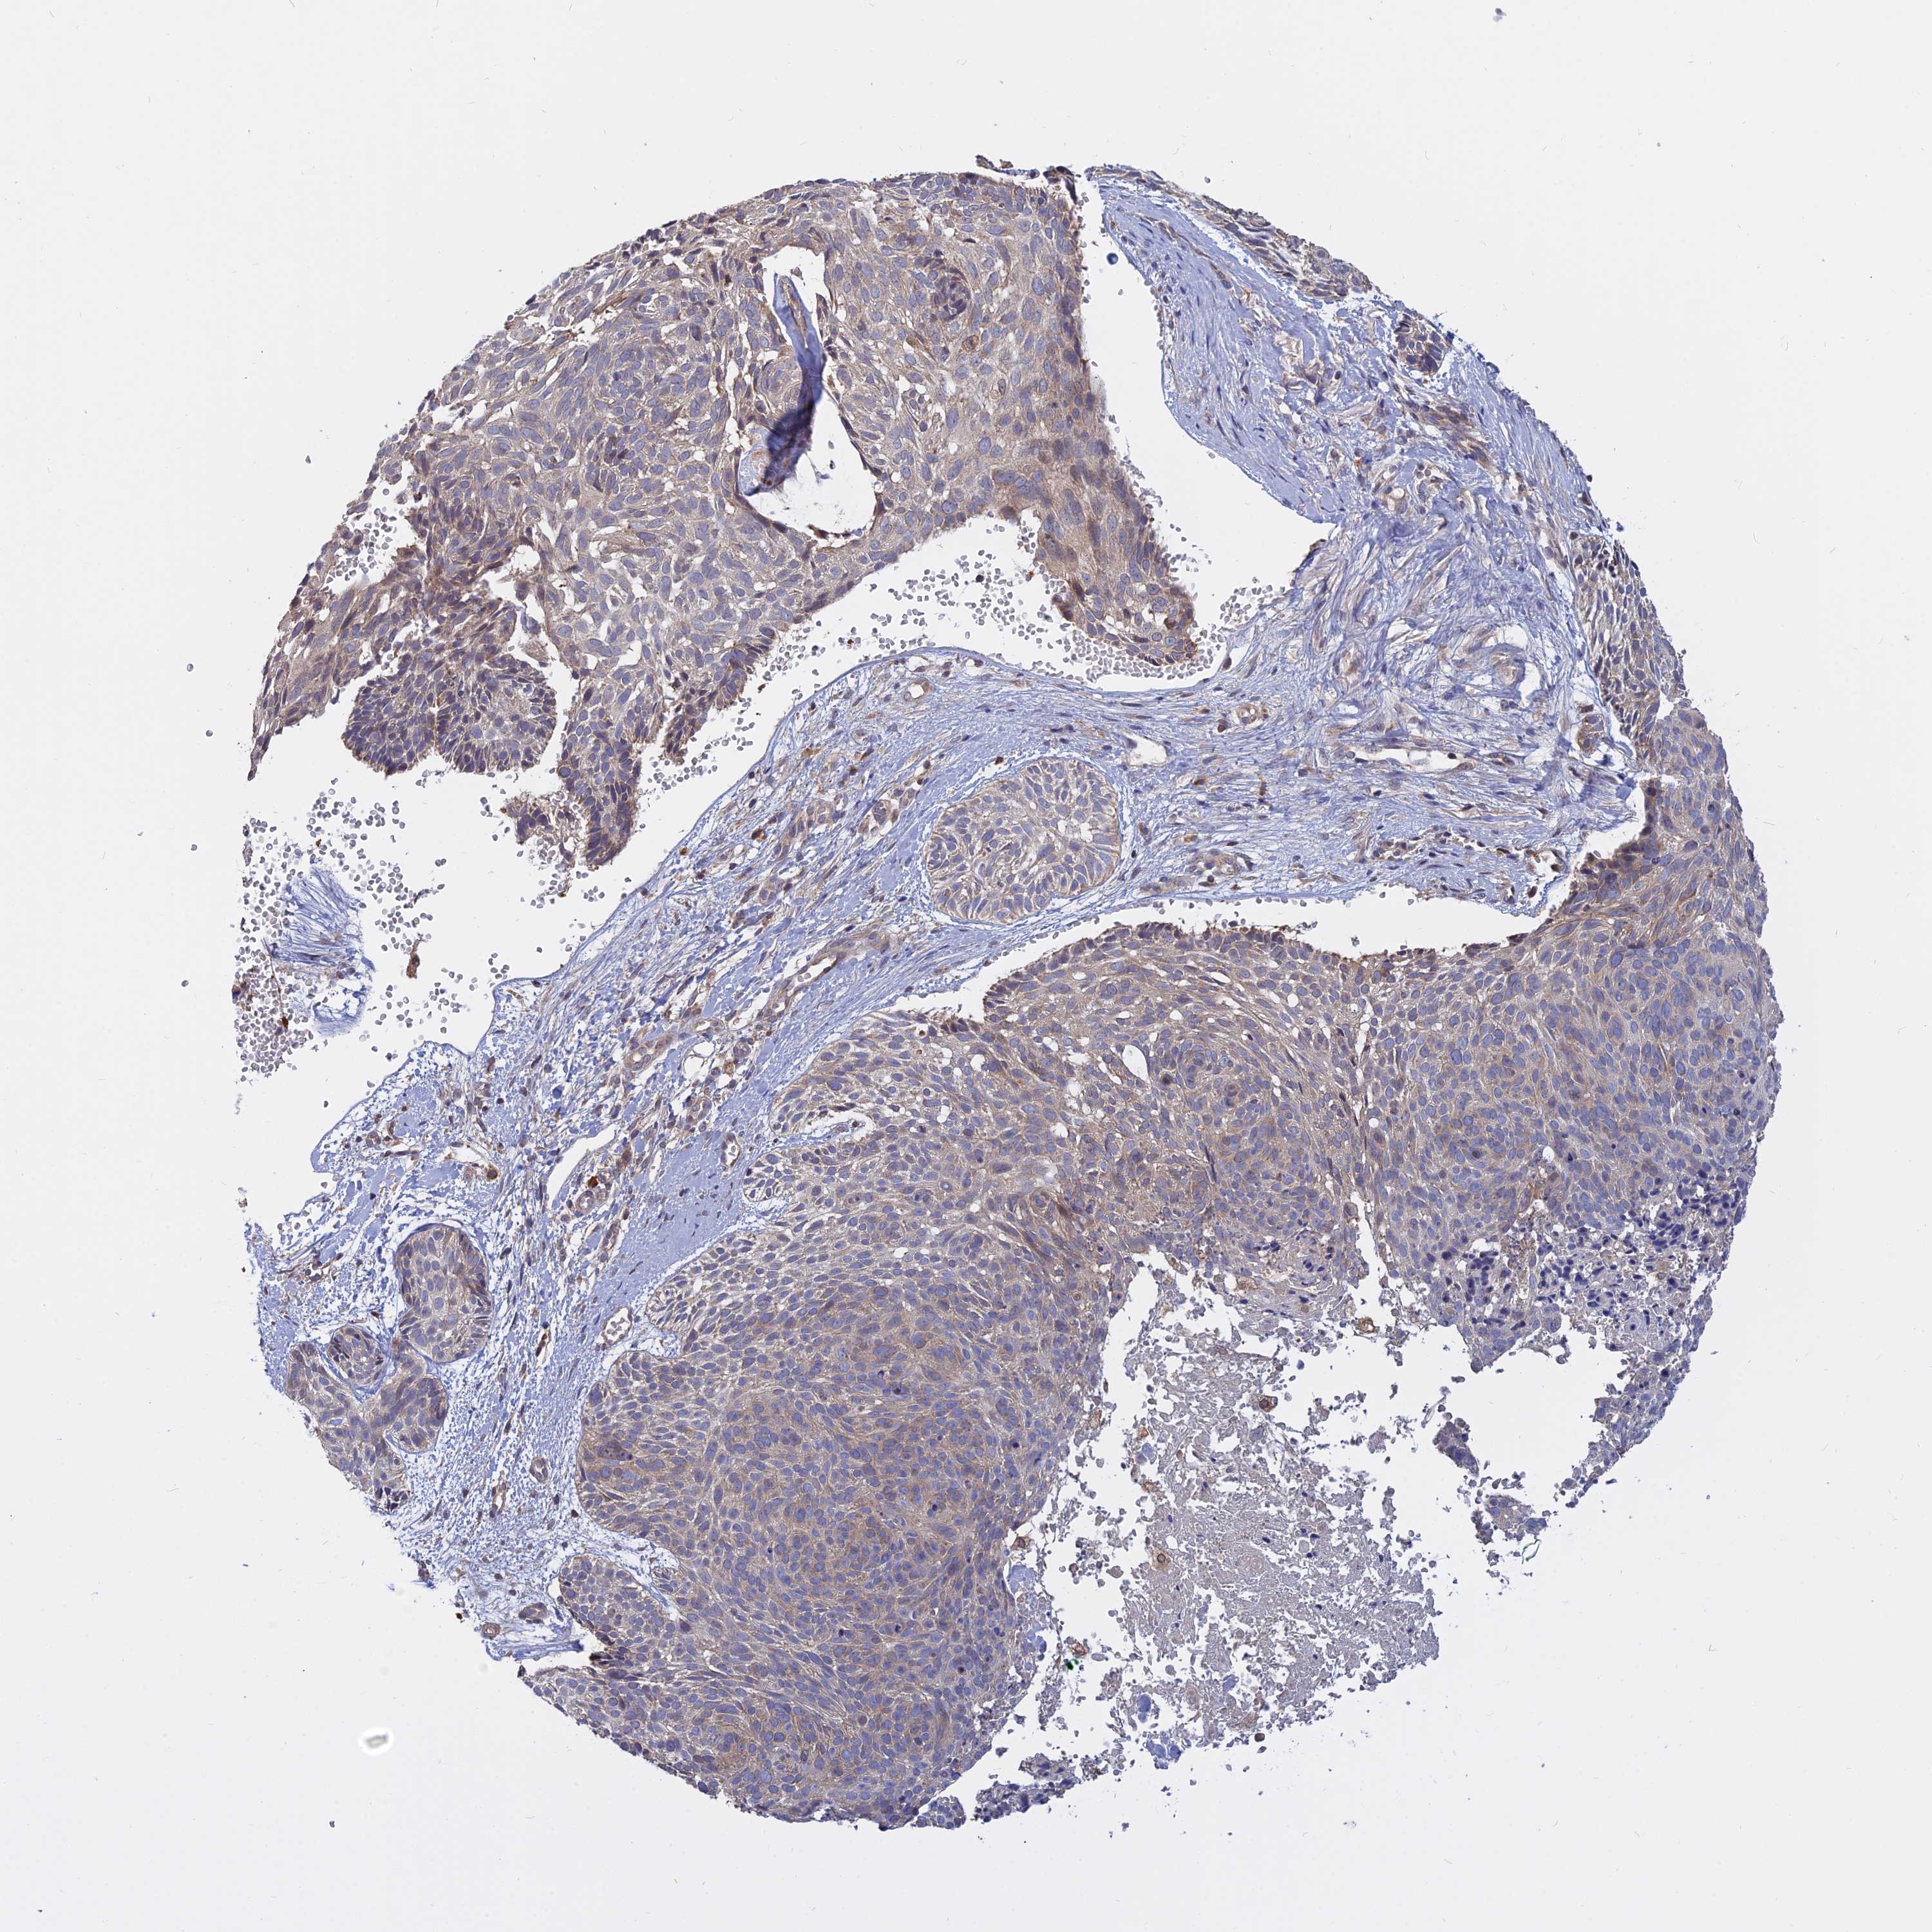

SKIN CANCER - Protein expressioni

A mouse-over function shows sample information and annotation data. Click on an image to view it in a full screen mode. Samples can be filtered based on level of antibody staining by selecting one or several of the following categories: high, medium, low and not detected. The assay and annotation is described here.

Antibody stainingi

Antibody staining in the annotated cell types in the current human tissue is reported as not detected, low, medium, or high, based on conventional immunohistochemistry profiling in selected tissues. This score is based on the combination of the staining intensity and fraction of stained cells.

Each image is clickable and will lead to virtual microscopy that enables deeper exploration of all samples and also displays staining intensity scores, fraction scores and subcellular localization as well as patient and tissue information for each sample.

Antibody HPA042296

Staining

High

Medium

Low

Not detected

Intensity

Strong

Moderate

Weak

Negative

Quantity

>75%

75%-25%

<25%

None

Location

Nuclear

Cytoplasmic/membranous

Cytoplasmic/membranous,nuclear

Squamous cell carcinoma, NOS